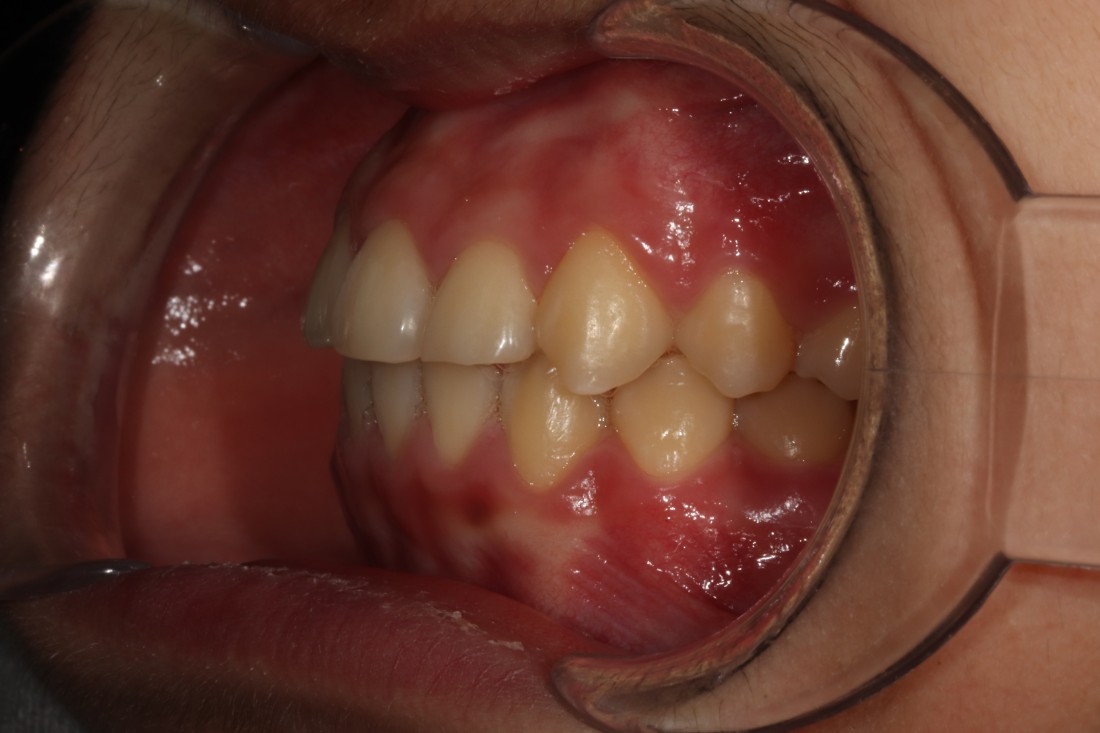

광주 덧니교정 치과에서는

덧니교정 시에

발치를 하는 경우도 있고,

비발치로 진행하는 경우도 있습니다.

치료계획은 모두 경험이 풍부한

교정전문의 대표원장님과

교정 전 정밀검사 결과를 토대로

오랜시간 세심한 상담 후에

결정하고 있습니다.

교정전문의가 봤을 때

발치가 꼭 필요한 경우가 있기 때문에

다양한 덧니교정 케이스와 비교하며

나만을 위한 치료계획을 세우고 있습니다.